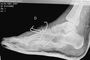

Max Neukirchner: So sah der Fuss mit Drähten aus.

«Nach fünf Minuten war alles gelaufen», erklärte Max Neukirchner, als er um 8.30 Uhr aus dem Operationssaal der Athromed-Klinik in Chemnitz kam. Die Drähte in seinem rechten Fuss, den er sich beim Crash in Monza mehrfach gebrochen hatte, wurden mit einer Zange herausgezogen. «Ich habe nichts gemerkt, der Arzt hat sehr professionelle Arbeit geleistet», stellte der Stollberger fest.